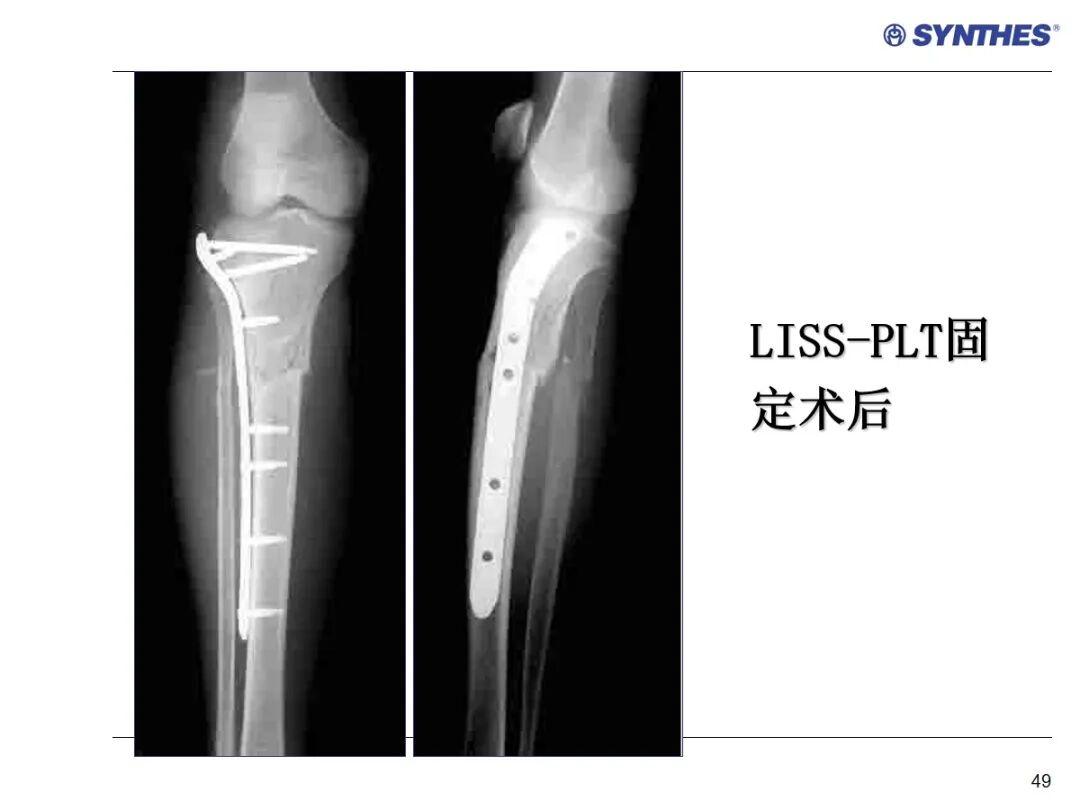

LISS微创固定系统应用技巧,原来如此简单!